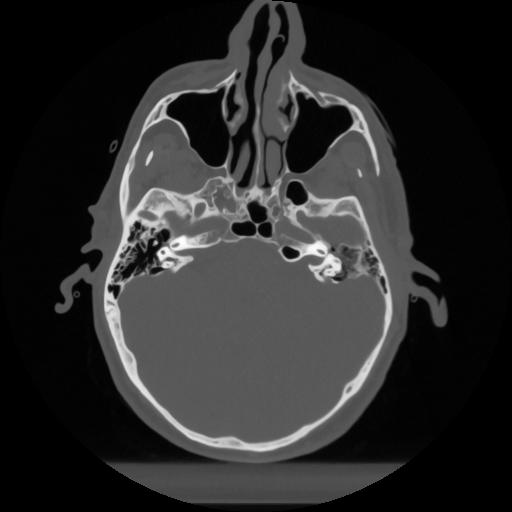

12 P.BLANDAS,,Vol,0.5,P.BLANDAS,,